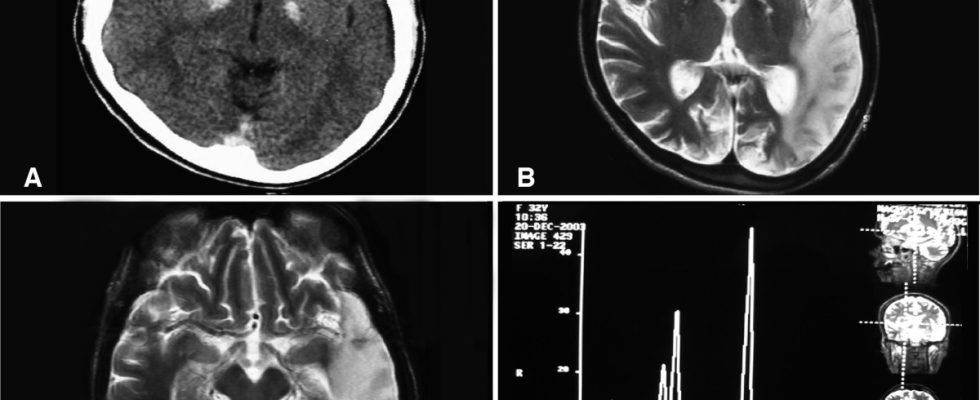

Illustrative photo by Abu-Amero KK, Al-Dhalaan H, Bohlega S, Hellani A, Taylor RW. [CC-BY-2.0], via Wikimedia Commons